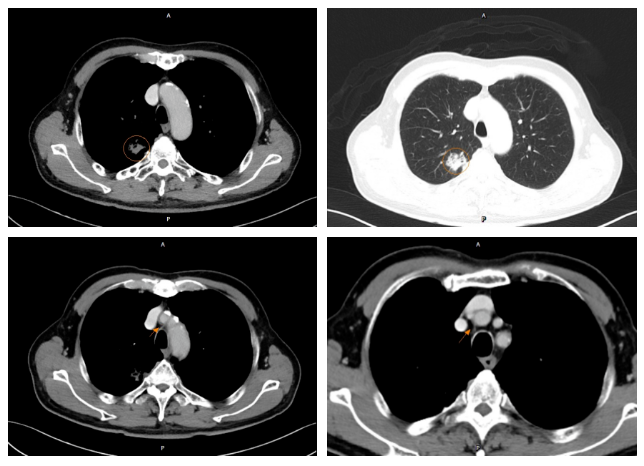

胸部CT:右肺上叶尖段见一混合密度结节,形态不规整,其内见多发小空泡,截面积22mmX18mm,边界不清,局部与胸膜粘连。

图7. 2022-05-18 CT:结合MRD随访考虑淋巴结转移